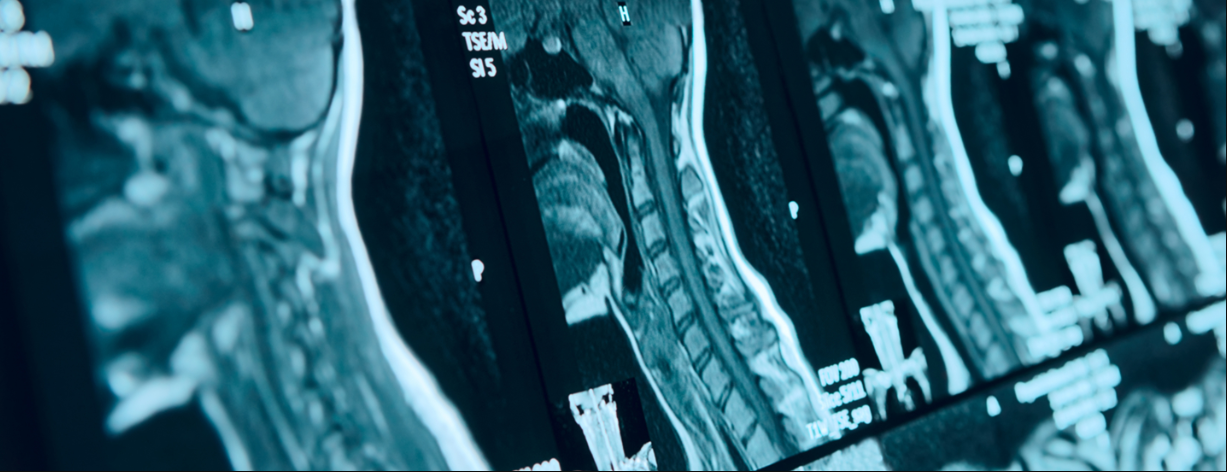

- Chụp cộng hưởng từ (MRI) sẽ giúp cung cấp các hình ảnh mô mềm, đồng thời giúp xác định xem Gãy cột sống cổ có gây tổn thương tủy sống hay không.